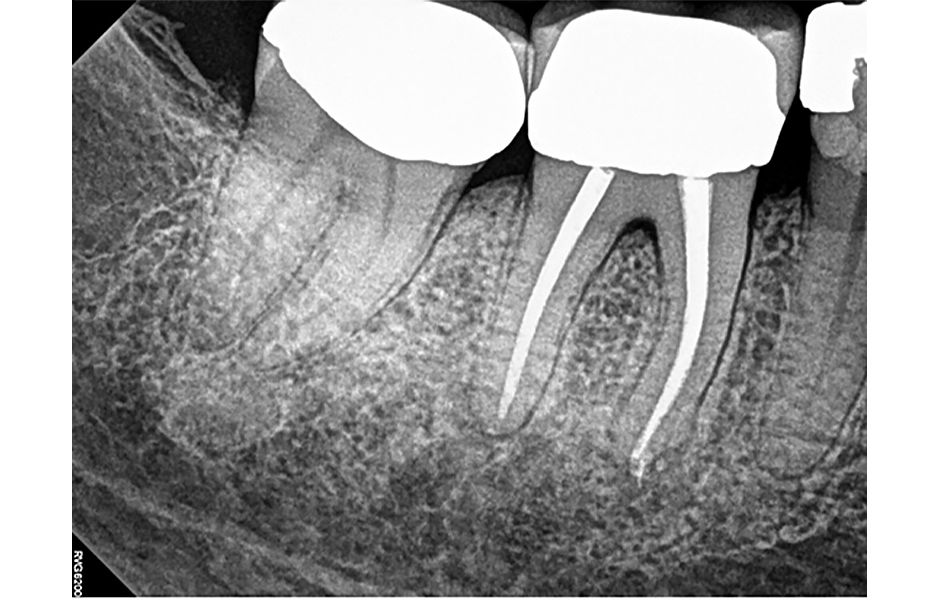

Pro radiologickou diagnostiku byl pořízen periapikální (PA) rentgenový snímek (obr. 1) a CBCT snímek s omezeným zorným polem (obr. 2a–d). Předchozí endodontické ošetření zahrnovalo zaplnění tří kanálků s nedostatečnou hustotou výplně v apikální třetině meziálních a distálních kořenů. V oblasti apexů meziálních (3 × 3 mm) a distálních (3 × 5 mm) kořenů byla patrná periapikální projasnění. CBCT (obr. 2a–d) potvrdilo nezaplněný distolingvální (DL) kanálek a možný střední meziální (MM) kanálek; koronální CBCT řez meziálního kořene (obr. 2c) také naznačuje přítomnost apikální delty spíše než jediného apikálního foramenu. Nebyly zjištěny žádné známky prasklin či fraktur.

Obr. 1: Předoperační PA rentgenový snímek zubu 46.

Obr. 2a, b: Předoperační CBCT řezy zubu 46 – a) sagitální, b) axiální.

Obr. 2c, d: Předoperační CBCT řezy zubu 46 – c) meziální kořen, d) distální kořen.